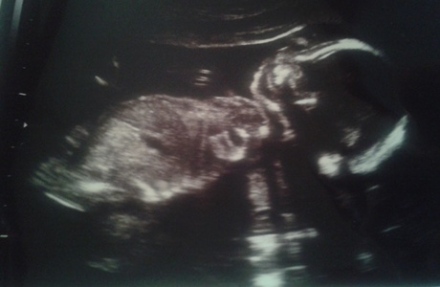

Terhesnapló 6. - Miért is menne minden zökkenőmentesen?

Túl vagyok a vizsgálatokon és a konzultáción, már ha ezt lehet annak nevezni, de erről majd később. Hétfő délelőtt megjelentem a huszadik heti genetikai ultrahangon, férjestől, gyerekestől. Egy pillanatig eszembe nem jutott, hogy bármi gond is...